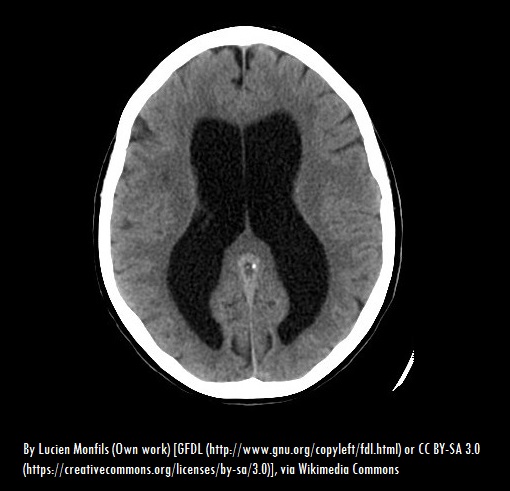

Hydrocephalus also known as “water on the brain” is the build-up of cerebrospinal fluid in the brain cavity. Cerebrospinal fluid normally flows through the cavities and bathes the brain and the spinal column but the pressure caused by too much fluid can damage the brain tissues and cause impairments in brain function (mayoclinic.org).

Hydrocephalus is commonly treated by using a shunt which is a long flexible tube with a valve whose one end is placed in one of the brain’s ventricles. The shunt helps act as a drainage system which re-directs the cerebrospinal fluid to a part of the body which can easily absorb it such as the abdomen.

Another form of treatment is Endoscopic of the Third Ventriculostomy which involves the surgical creation of a hole at the bottom or between the brain’s ventricle creating a passage for cerebrospinal fluid to flow out of the brain.